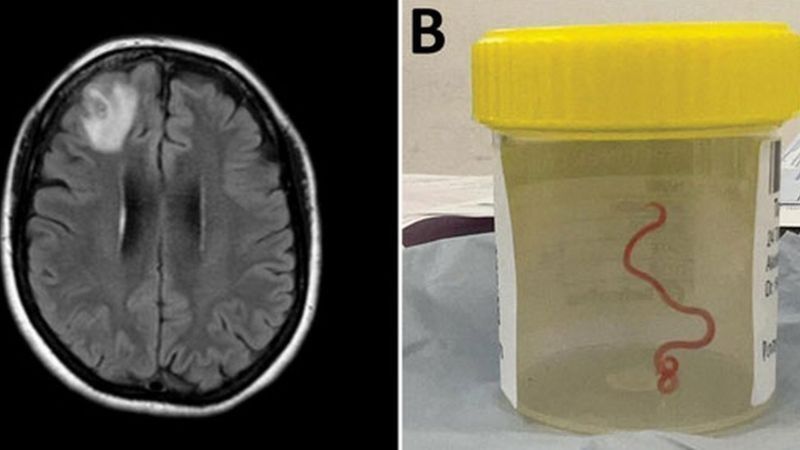

En un caso nunca antes documentado en el mundo, científicos informaron que encontraron un gusano vivo de 8 cm en el cerebro de una mujer en Australia.

La "estructura en forma de cuerda" fue extraída del lóbulo frontal lesionado de la paciente durante una cirugía en Canberra el año pasado.

Los médicos dijeron que el parásito rojo pudo haber estado vivo en el cerebro de la mujer hasta por dos meses.

El nematodo extraído del cerebro de una mujer.

"Todos en ese quirófano sufrieron el shock de su vida cuando [la cirujana] tomó unas pinzas para detectar una anormalidad y la anormalidad resultó ser un gusano vivo, de color rojo claro, de 8 cm, que se retorcía", dijo la doctora Sanjaya Senanayake, especialista en enfermedades infecciosas del Hospital de Canberra.

Un escáner cerebral y el nematodo extraído en un frasco de muestras,